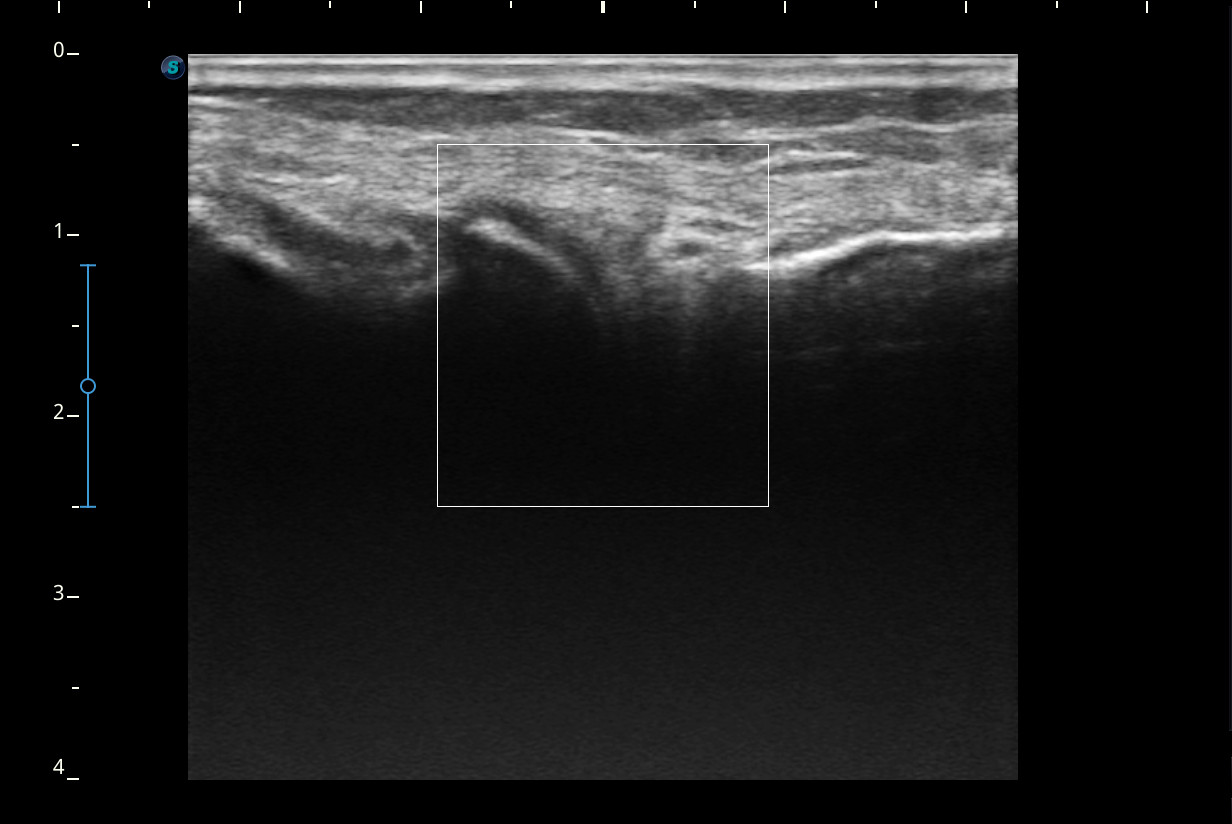

Se realiza ecografía de rodilla.

Descripción de los hallazgos ecográficos y las imágenes más relevantes para la resolución del caso

Rodilla sin derrame articular. No se aprecian lesiones en Ligamentos colaterales. Ligamento rotuliano sin hallazgos valorables. Rotura menisco interno y dudosa fisura menisco externo. Tendones rotuliano y cuadricipital normales.